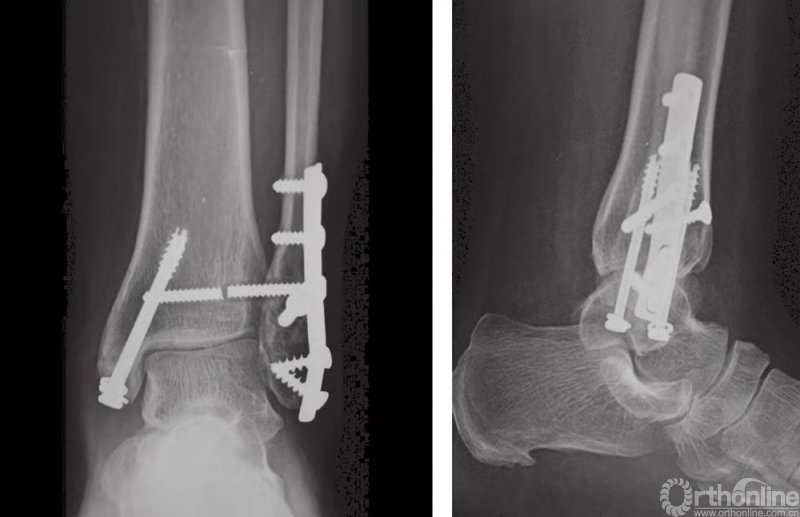

通常在10周之后取出下胫腓联合螺钉,随后患者开始完全负重。在开始负重前,一些外科医生更倾向于不取出下胫腓联合螺钉。但在这种情况下,须事先告知患者术后的负重可能会导致下胫腓联合螺钉破裂(图26)。

图26 术后16周下胫腓螺钉断裂,但患者无症状